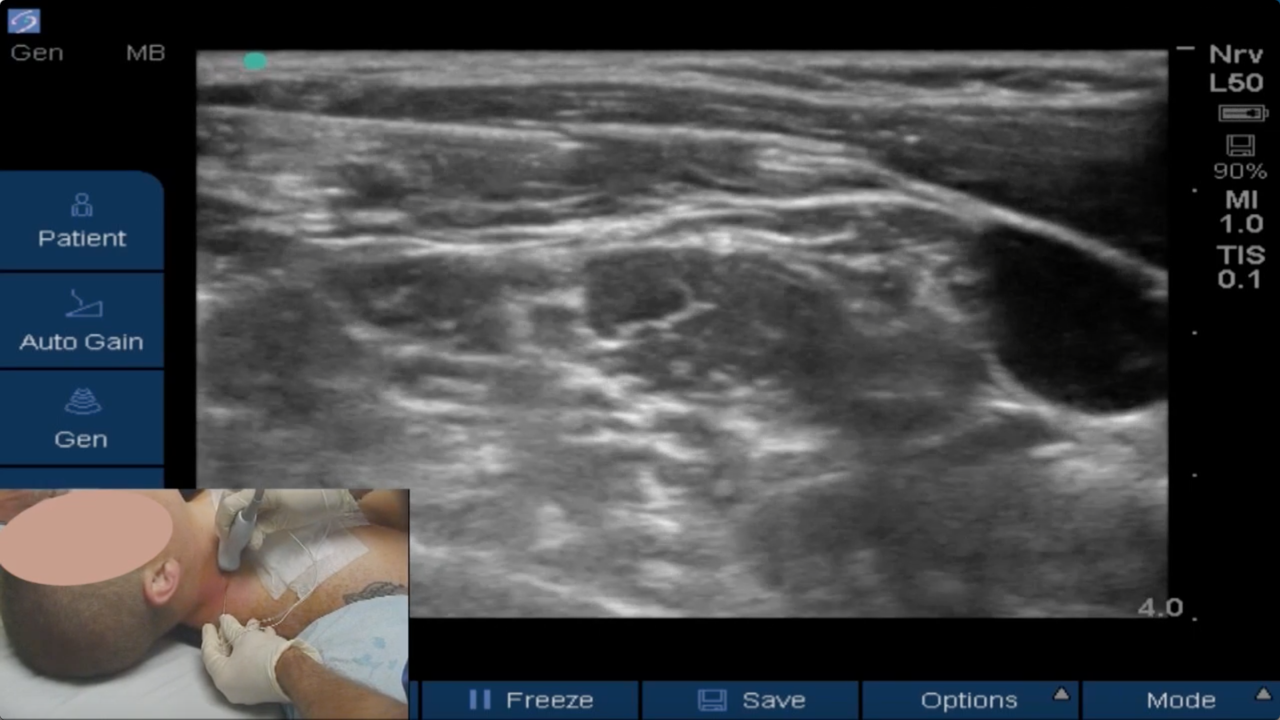

Brandon Winchester performs a rescue ultrasound-guided superficial cervical plexus block in the PACU for medial clavicle surgery, and ultimately needs to perform an additional interscalene block for complete pain relief.

Brandon Winchester, MD, regional anesthesia fellowship director at the Andrews Institute, performs an ultrasound-guided superficial cervical plexus rescue block to treat severe breakthrough pain in the PACU after sternoclavicular joint reconstruction & medial claviculectomy surgery.